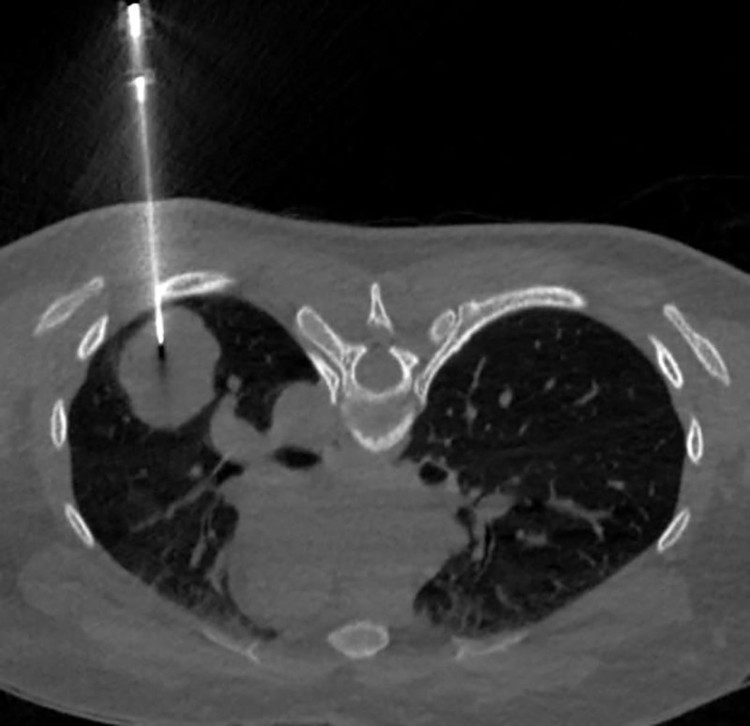

Kết quả chụp CT lồng ngực có tiêm cản quang cho thấy hình ảnh u thùy dưới phổi trái/Ảnh Medlatec

Chụp CT lồng ngực có tiêm cản quang phát hiện khối u thùy dưới phổi trái (LUNG-RADS 4B), kèm theo nốt nhỏ thùy giữa phổi phải, cần loại trừ tổn thương thứ phát.